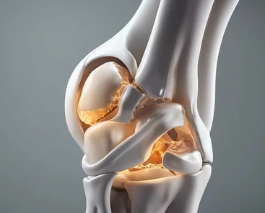

**퇴행성 관절염(Osteoarthritis)**은 나이가 들면서 관절의 연골이 닳아 없어지고, 관절을 이루는 뼈와 인대에 변화가 생겨 통증과 운동 제한이 나타나는 질환입니다. 흔히 ‘나이 들어 생기는 관절병’이라고도 불리며, 무릎, 손가락, 고관절, 척추 등 하중을 받는 관절에 주로 발생합니다. 이번 글에서는 퇴행성 관절염의 대표적인 증상, 초기·중기·말기별 변화, 감별 질환, 진단 및 관리법까지 자세히 정리합니다.

2. 증상 진행 단계별 특징

구분 증상 특징

| 초기 |

- 관절 사용 후 불편함

- 일시적인 통증

- 뻣뻣하지만 회복 빠름 | | 중기 |